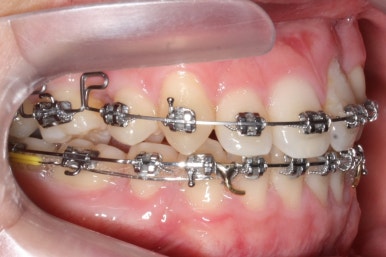

좁아져 있는 위턱뼈를 가로로 넓혀주기 위해서 악궁확장장치를 사용했습니다.

윗니는 선천결손으로 치아가 2개가 모자랐고 앞니도 거꾸로 물리는 상황이여서 아랫니도 균형있게 2개를 추가로 더 뽑았습니다.

악궁확장과 동반하여 부산구순구개열 키다리아저씨치과에서는 브라켓을 부착하여 가지런하게 하는 작업을 시작하였습니다.

위아랫니가 각각 가지런해지고 있는 것을 볼 수 있습니다.

적절한 시기가 되면 악궁확장장치를 제거하고, 확장장치가 걸려있던 치아도 가지런하게 해줍니다.

윗니는 아직 가지런하게 하는 작업 중이며, 아랫니는 가지런하게 하는 작업은 거의 다 되었습니다.

이제 아랫니는 이 뽑은 자리를 앞뒤로 당겨서 없애주어야 합니다. 보통은 앞니가 뒤로 많이 들어오기 때문에 이번 환자분 처럼 앞니가 거꾸로 물리는 경우 앞니를 제대로 물리게 해줄 수 있습니다.

계속 윗니는 가지런히 해주고 있으며 아랫니는 앞뒤를 뒤로 당기고 있습니다.

거꾸로 물리던 앞니가 서서히 개선되어 가는 것을 볼 수 있습니다.